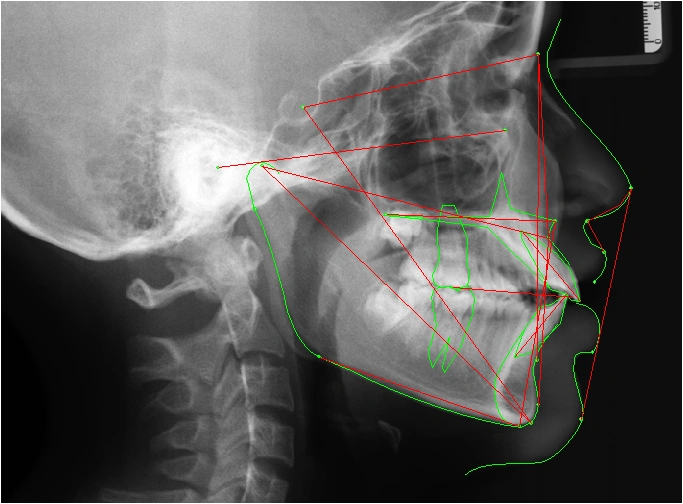

Để chẩn đoán và lập kế hoạch điều trị chỉnh nha tốt nhất. Hệ thống máy chụp phim panorama và cefalo kỹ thuật số, tích hợp phần mềm bản quyền Align Pro. Trang bị này cho phép bác sĩ chỉnh nha chẩn đoán, lập kế hoạch và điều trị giả định.